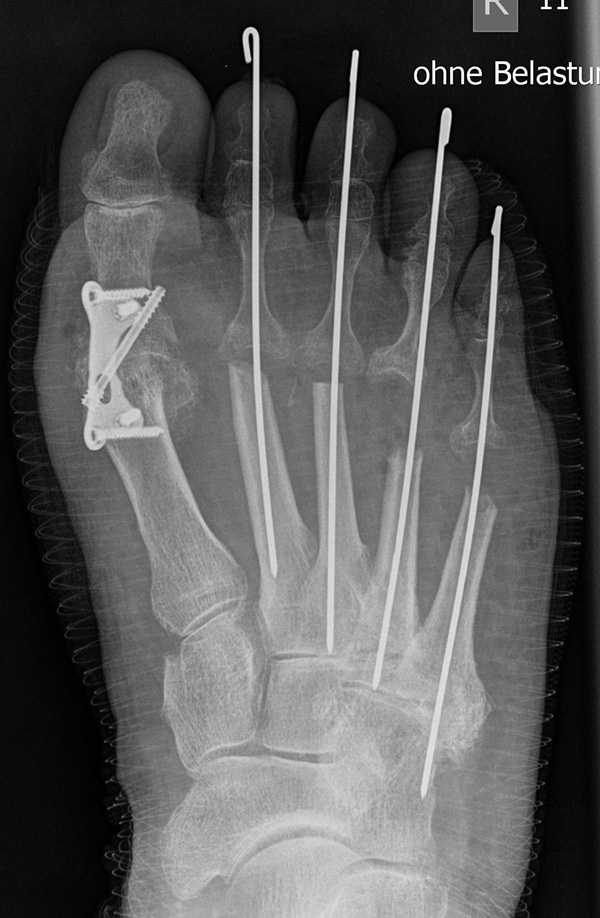

Deutlich bessere Ergebnisse wurden erreicht durch eine Kombination der OP nach Tillmann mit einer Arthrodese des Großzehengrundgelenks oder auch einer Lapidus-Arthrodese 611. Dies wurde bereits 1956 durch Vainio empfohlen, hat sich aber erst in diesem Jahrtausend flächendeckend durchgesetzt 121314.

Die Operation nach Hoffmann-Tillmann (Abb. 4) ermöglicht durch die Resektion der Metatarsaleköpfe die Reposition der Zehen, da hierdurch der notwendige Platz geschaffen wird (Tillmann 1990). Meist sind nicht nur die knöchernen Strukturen der Metatarsaleköpfe destruiert, auch das plantare Polster ist disloziert, regelmäßig kommt es zur Ruptur der plantaren Platten mit Destruktion der Kapsel-, Band- und Sehnenstrukturen (Tillmann 2009) 6. Häufig findet man ausgeprägte Rheumaknoten oder Bursitiden plantar. Durch die breite, querovaläre Hautexzisionaus dem Vorfußballen werden plantare Schwielen entfernt, später beim Hautverschluß werden die plantaren Strukturen durch die plastische Dermatodese wieder in die Belastungszone reponiert.

Abschließend erfolgt die temporäre K-Daht Fixation sämtlicher Kleinzehen in achsgerechter Stellung. Die Strecksehnen werden in Verlängerung vernäht.

Die Arthrodese des Großzehengrundgelenks in Kombination mit einer Resektionsarthroplastik der Metatarsaleköpfchen der Kleinzehen führt zu guten klinischen Langzeitergebnissen bei Patienten mit rheumatoider Arthritis und destruiertem Metatarsaleköpfchen 34. Auch aktuelle Metaanalysen zeigen, dass dieses Verfahren den Standard bei dieser Pathologie darstellt und dass sich insbesondere auch gelenkerhaltende Therapieverfahren an diesen Ergebnissen messen müssen 35. Triolo et al. 11 berichteten über die Ergebnisse von 89 Füßen (62 Patienten) mit einem Follow up von mindestens 4 Jahren. Der AOFAS Score verbesserte sich nach Arthrodese am Großzehengrundgelenk und OP nach Tillmann Metatarsale II-V von präoperativ 33,4 ±16 auf 82,9 ± 11,9 Punkte. Schlechte Ergebnisse wurden beobachtet bei Patienten mit Revisionseingriffen aufgrund von Pseudarthrosen, verzögerter Knochenheilung, ungenügender Knochenresektion der Metatarsalia und störendem Osteosynthesematerial. Hulse et al. 36 verglichen die Ergebnisse nach Tillmann OP mit und ohne gleichzeitiger Resektion des Metatarsale I Kopfes. 44% der Patienten bei welchen das Großzehengrundgelenk erhalten wurde benötigten im 5-Jahres Follow-up einen weiteren Eingriff an diesem Gelenk. Die Autoren empfahlen daher, das Großzehengrundgelenk in jedem Fall in das Therapiekonzept einzubeziehen. Eine Langzeit Kohortenstudie an 203 Patienten (370 Füße) mit einem Follow-up von 11,4 Jahren wurde von Jüsten et al. veröffentlicht 10. 90,2% der Patienten berichteten über eine signifikante Besserung der Beschwerden, 87,5% über eine Besserung der Gehstrecke.